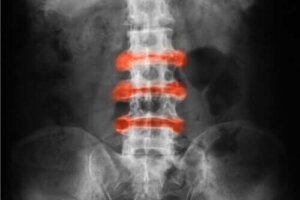

Zesztywniające zapalenie stawów kręgosłupa to zapalne zapalenie stawów, które występuje głównie w stawach pleców i miednicy. Ostre dolegliwości i sztywność ulegają poprawie wraz z aktywnością fizyczną, natomiast brak aktywności może je pogorszyć.

- Zesztywniające zapalenie stawów kręgosłupa: zapalenie stawów, które dotyczy głównie kręgosłupa.